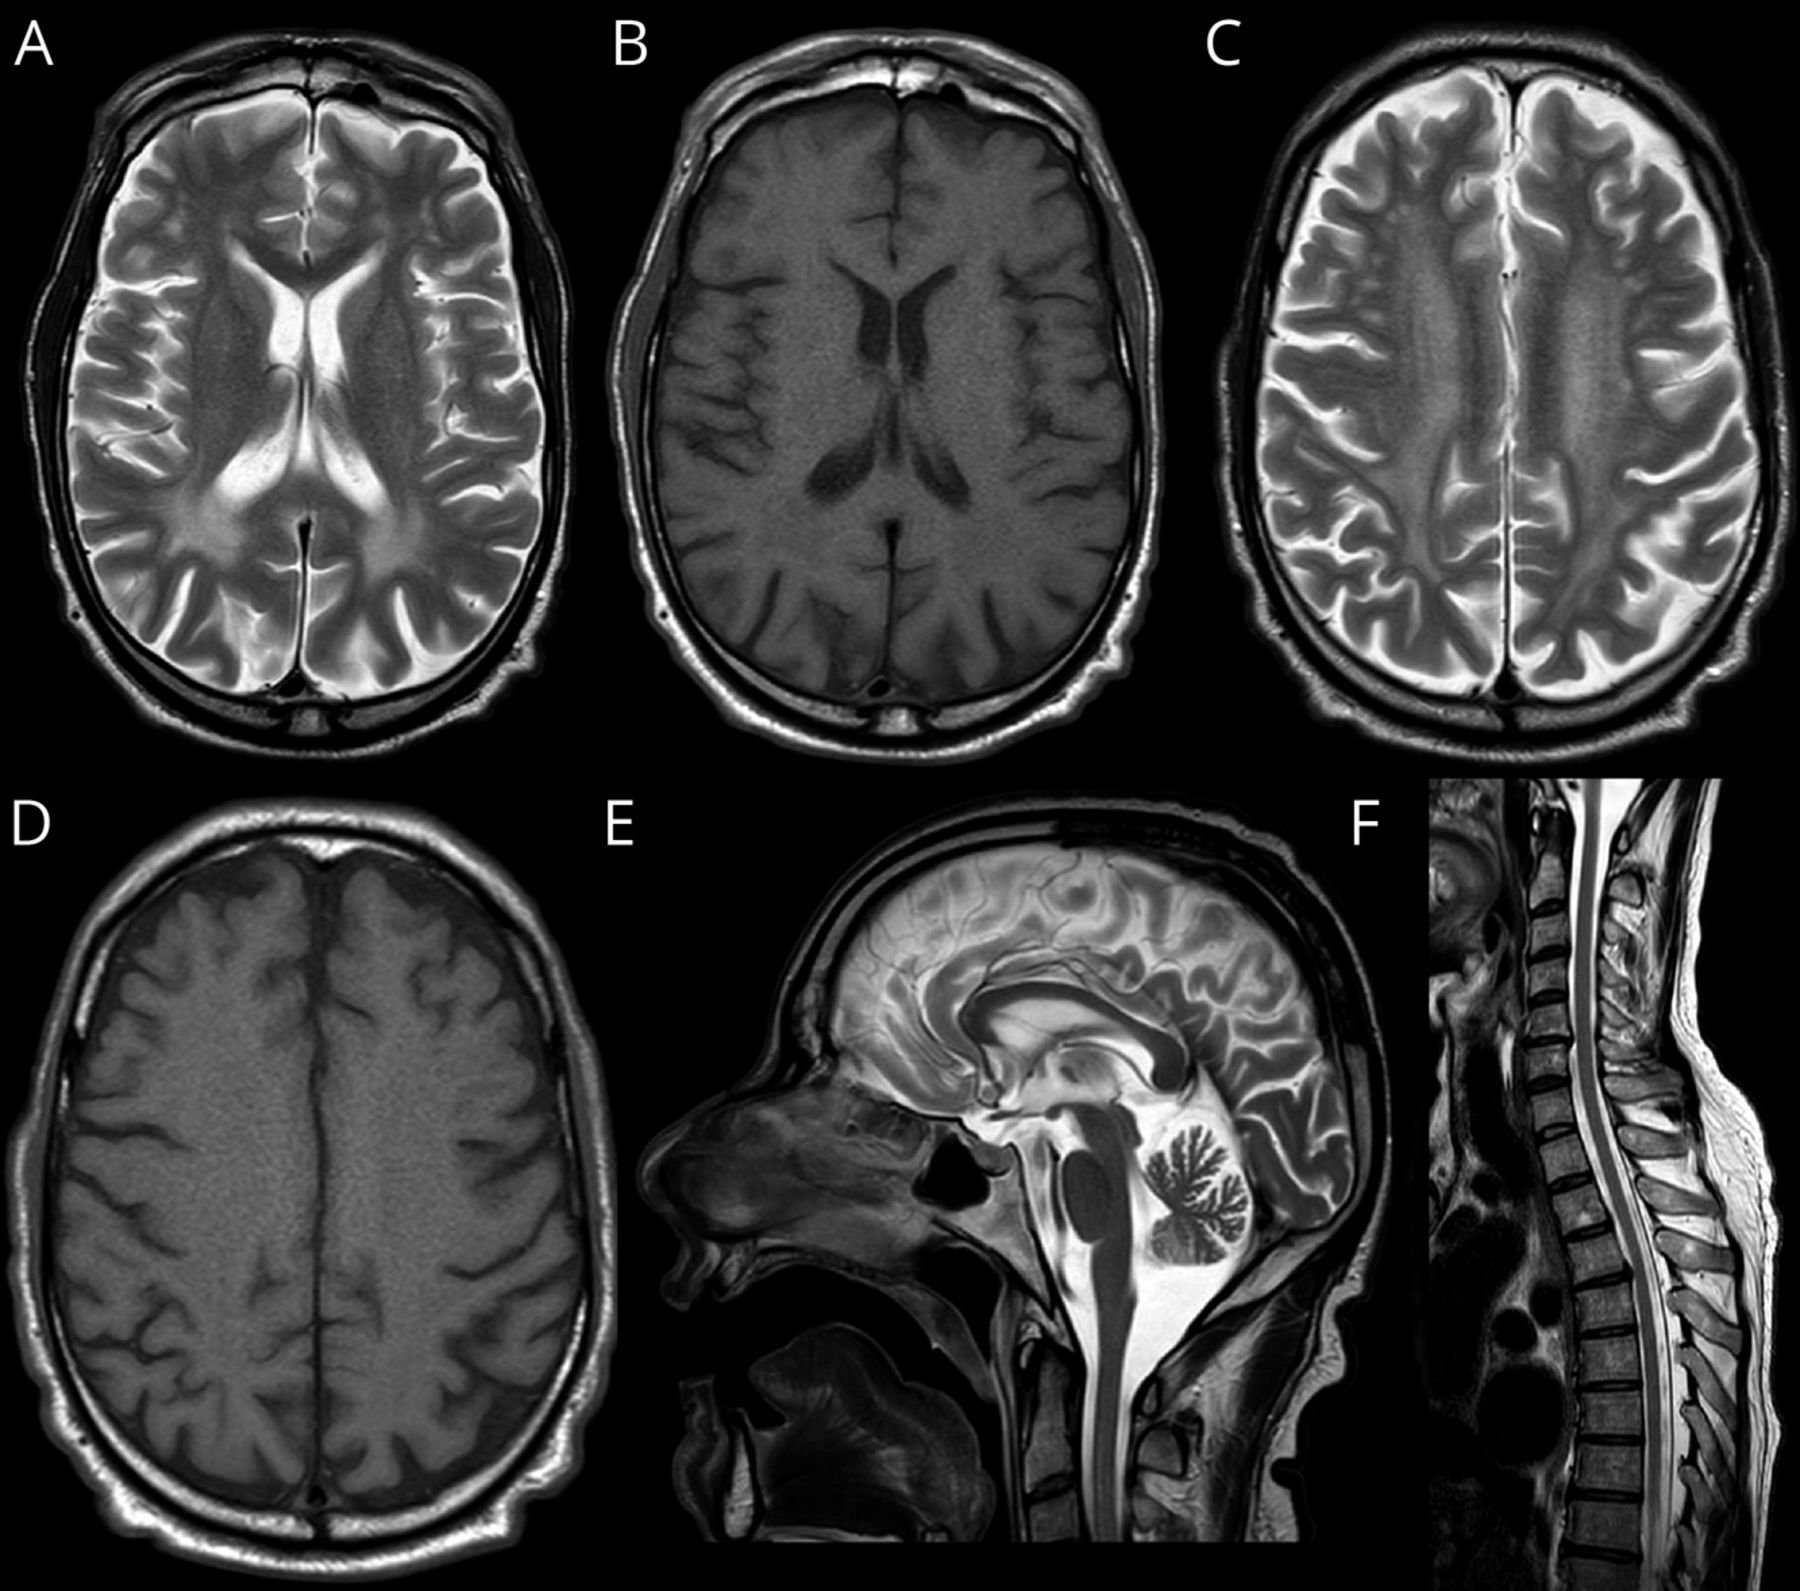

首先,由于痉挛性截瘫伴有上肢的快速反射,因此进行脊髓MRI检查,以确定该水平可能存在的颈髓病或其他结构性病变,结果正常(数字).随后行脑MRI,显示广泛的T2高信号累及深部,主要是后部,白质(WM),相应的T1信号轻度低信号,皮质下u纤维和胼胝体保留(数字).轻度小脑萎缩也存在。MR光谱(MRS)未见异常峰。由于慢性肾脏疾病,没有注射钆造影剂。

显示t2加权(A, C)和t1加权(B, D)基底神经节(A, B)和半卵圆椎体(C, D)水平轴向MRI扫描的面板。广泛对称的T2高信号(A, C)主要累及枕顶叶白质,对应T1轻度低信号(B),皮质下u型纤维和胼胝体保留。(E) t2加权矢状MRI扫描显示轻度蚓状小脑萎缩。(F)脊髓t2加权矢状MRI扫描。